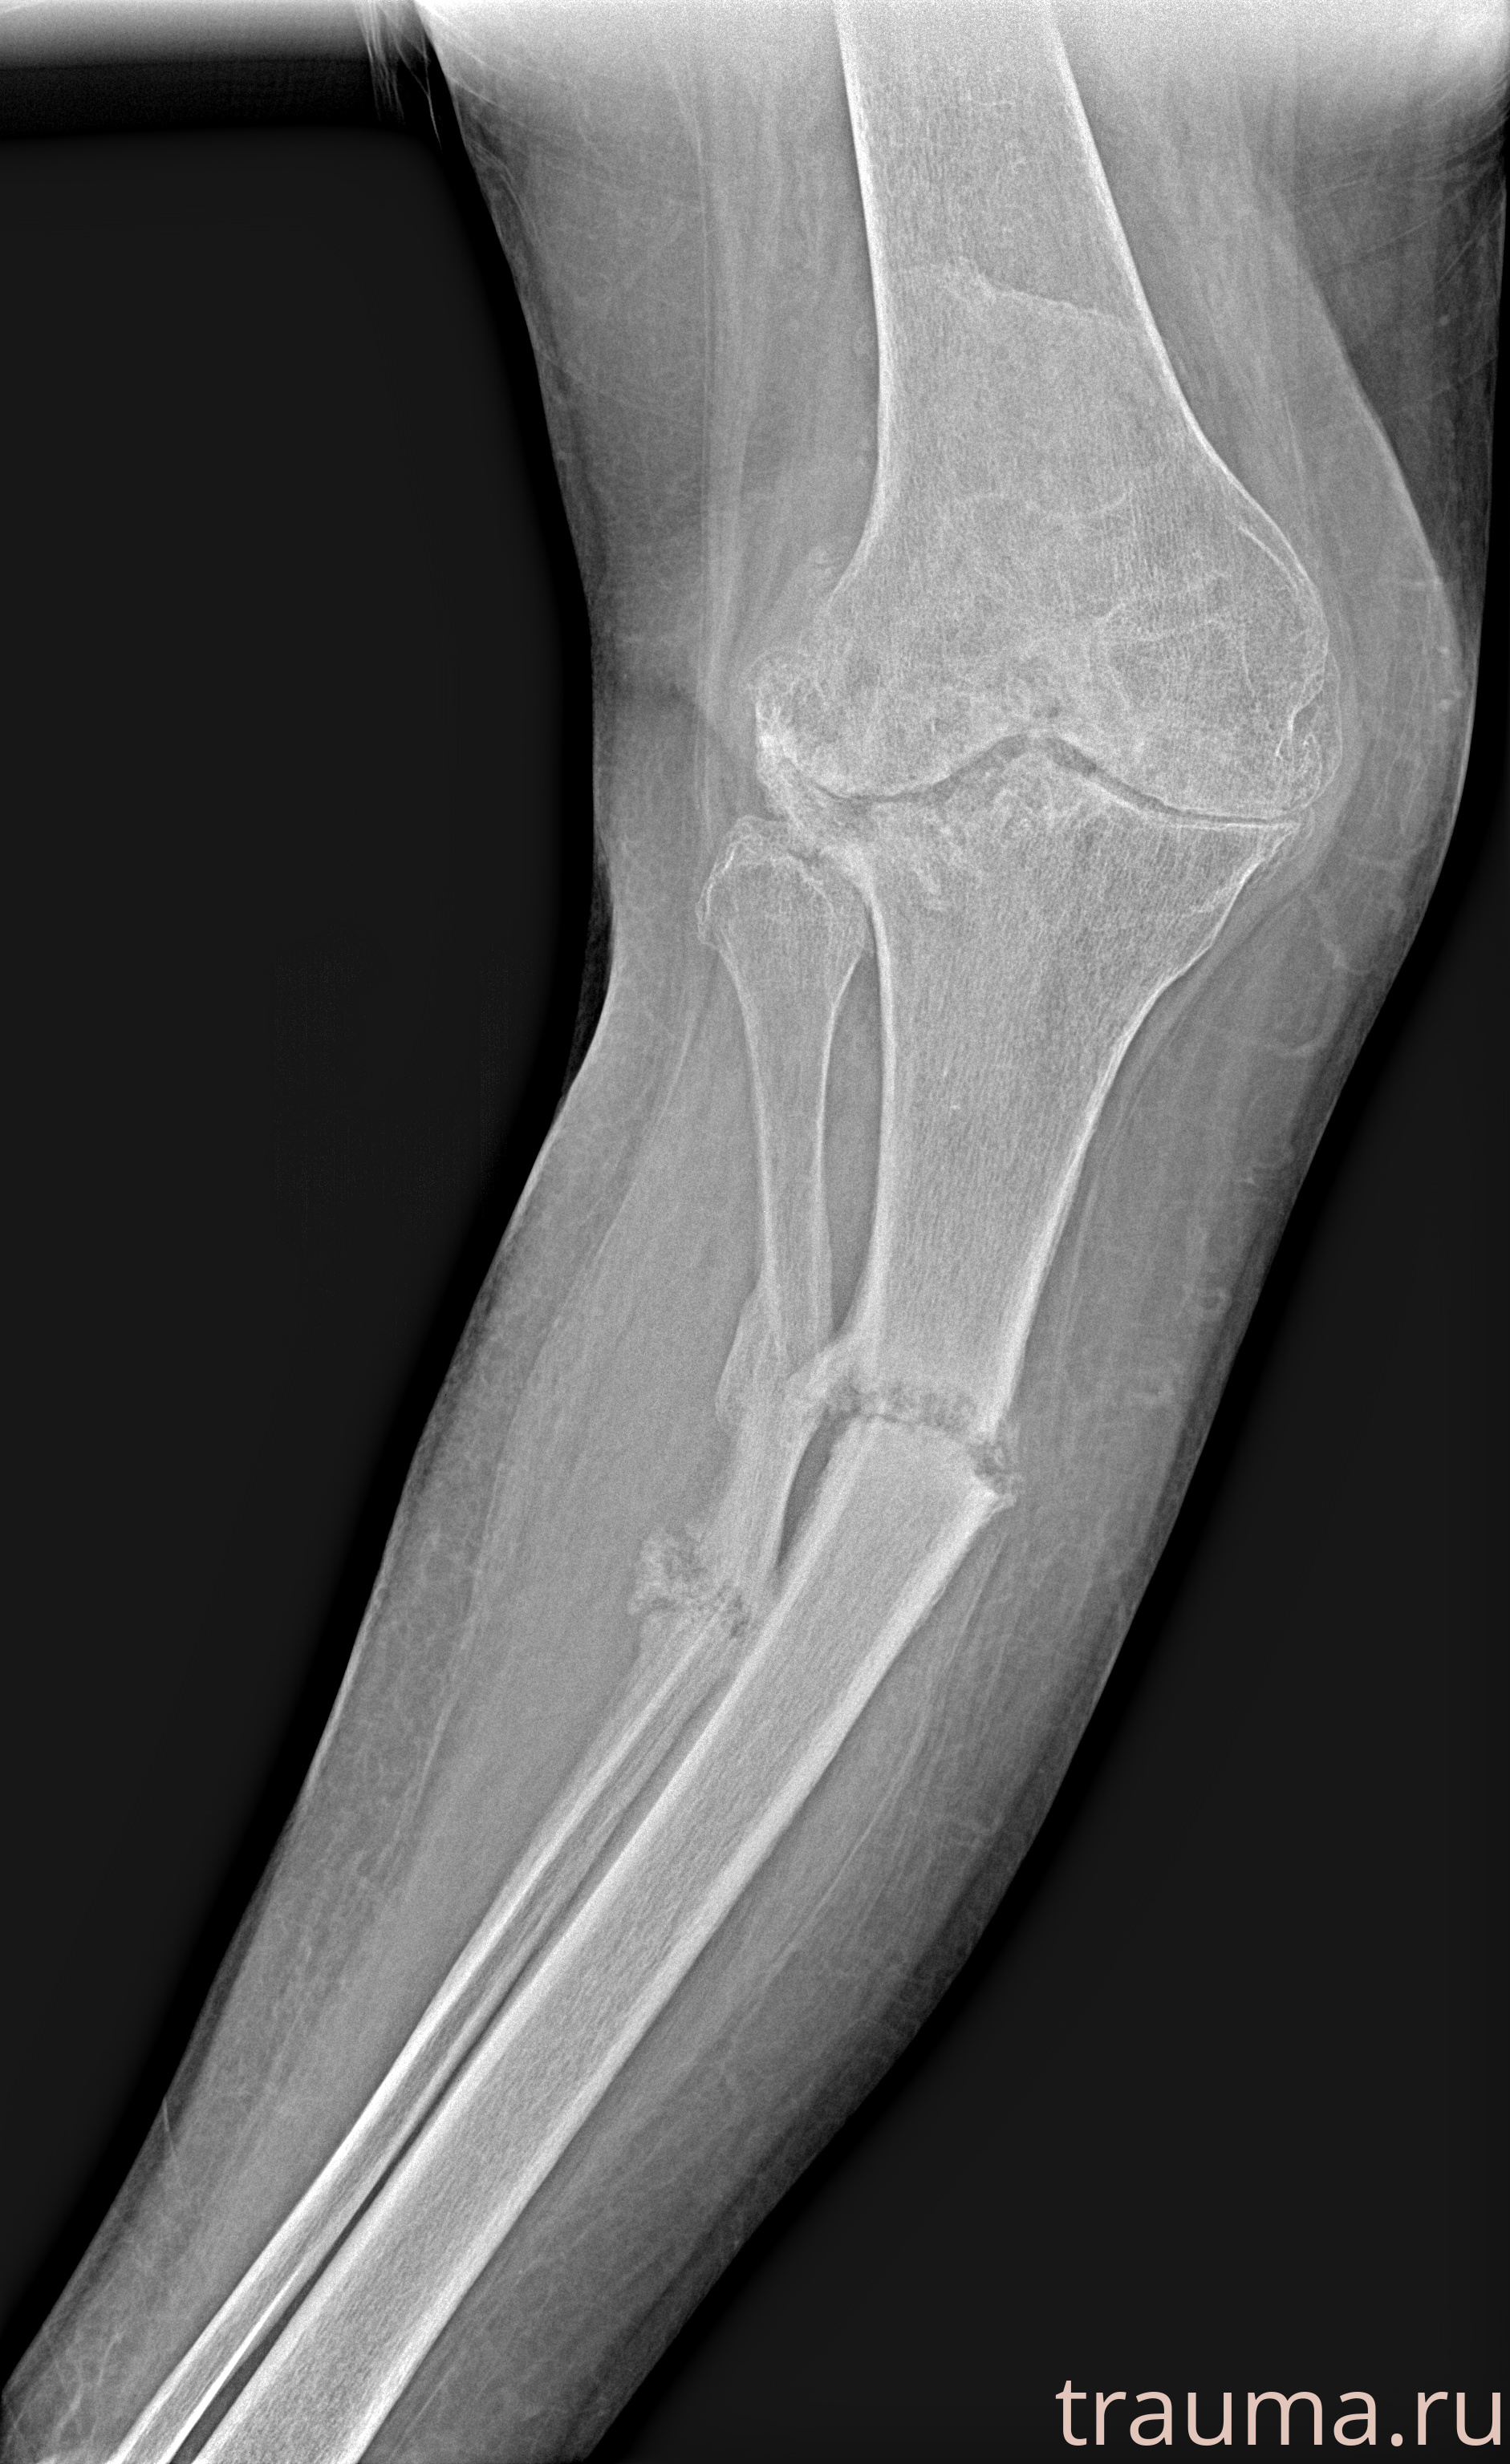

Рентгенограммы

Рентген на дому: по вашему адресу приезжает врач-рентгенолог, травматолог-ортопед с мобильным рентгеновским аппаратом, проводит диагностику травмы или заболевания, делает необходимые рентгенограммы, дает рекомендации по дальнейшему лечению. Получить качественные снимки в домашних условиях возможно благодаря уникальной методике, разработанной МосРентген Центром для института  Склифосовского